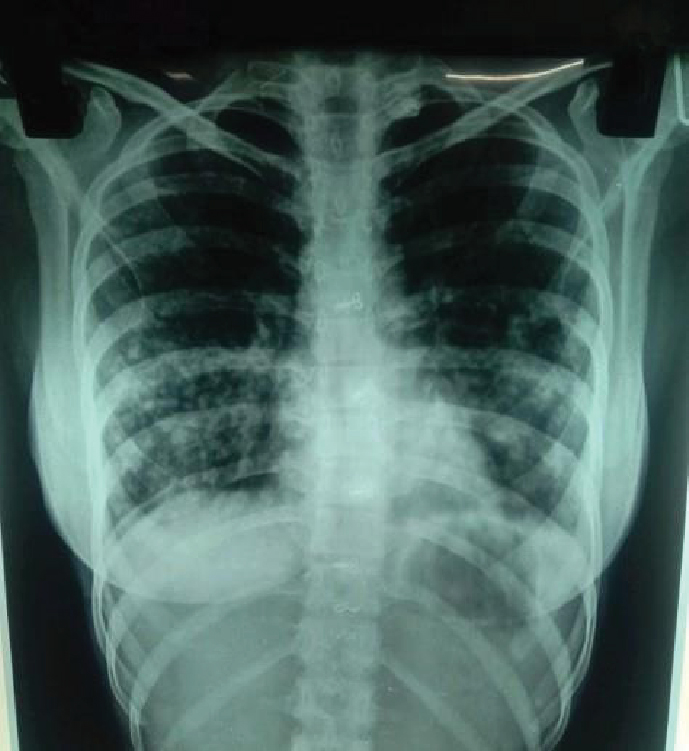

The patient had been well about 5 months back when she developed cough without expectoration, her chest X-ray revealed multiple heterogeneous opacities in bilateral lower zones (Fig. 1). Multiple sputum samples were obtained by inducing sputum production using 3% sodium chloride (NaCl) and were sent for microscopy, culture and cartridge-based nucleic acid amplification test (CBNAAT), but they were inconclusive. She was then started on directly observed treatment short-course (DOTS) antituberculosis treatment (ATT) empirically. There was no improvement in her symptoms but she continued ATT.

Figure 1. Chest X-ray (PA) - showing bilateral heterogeneous opacities in lower zones.